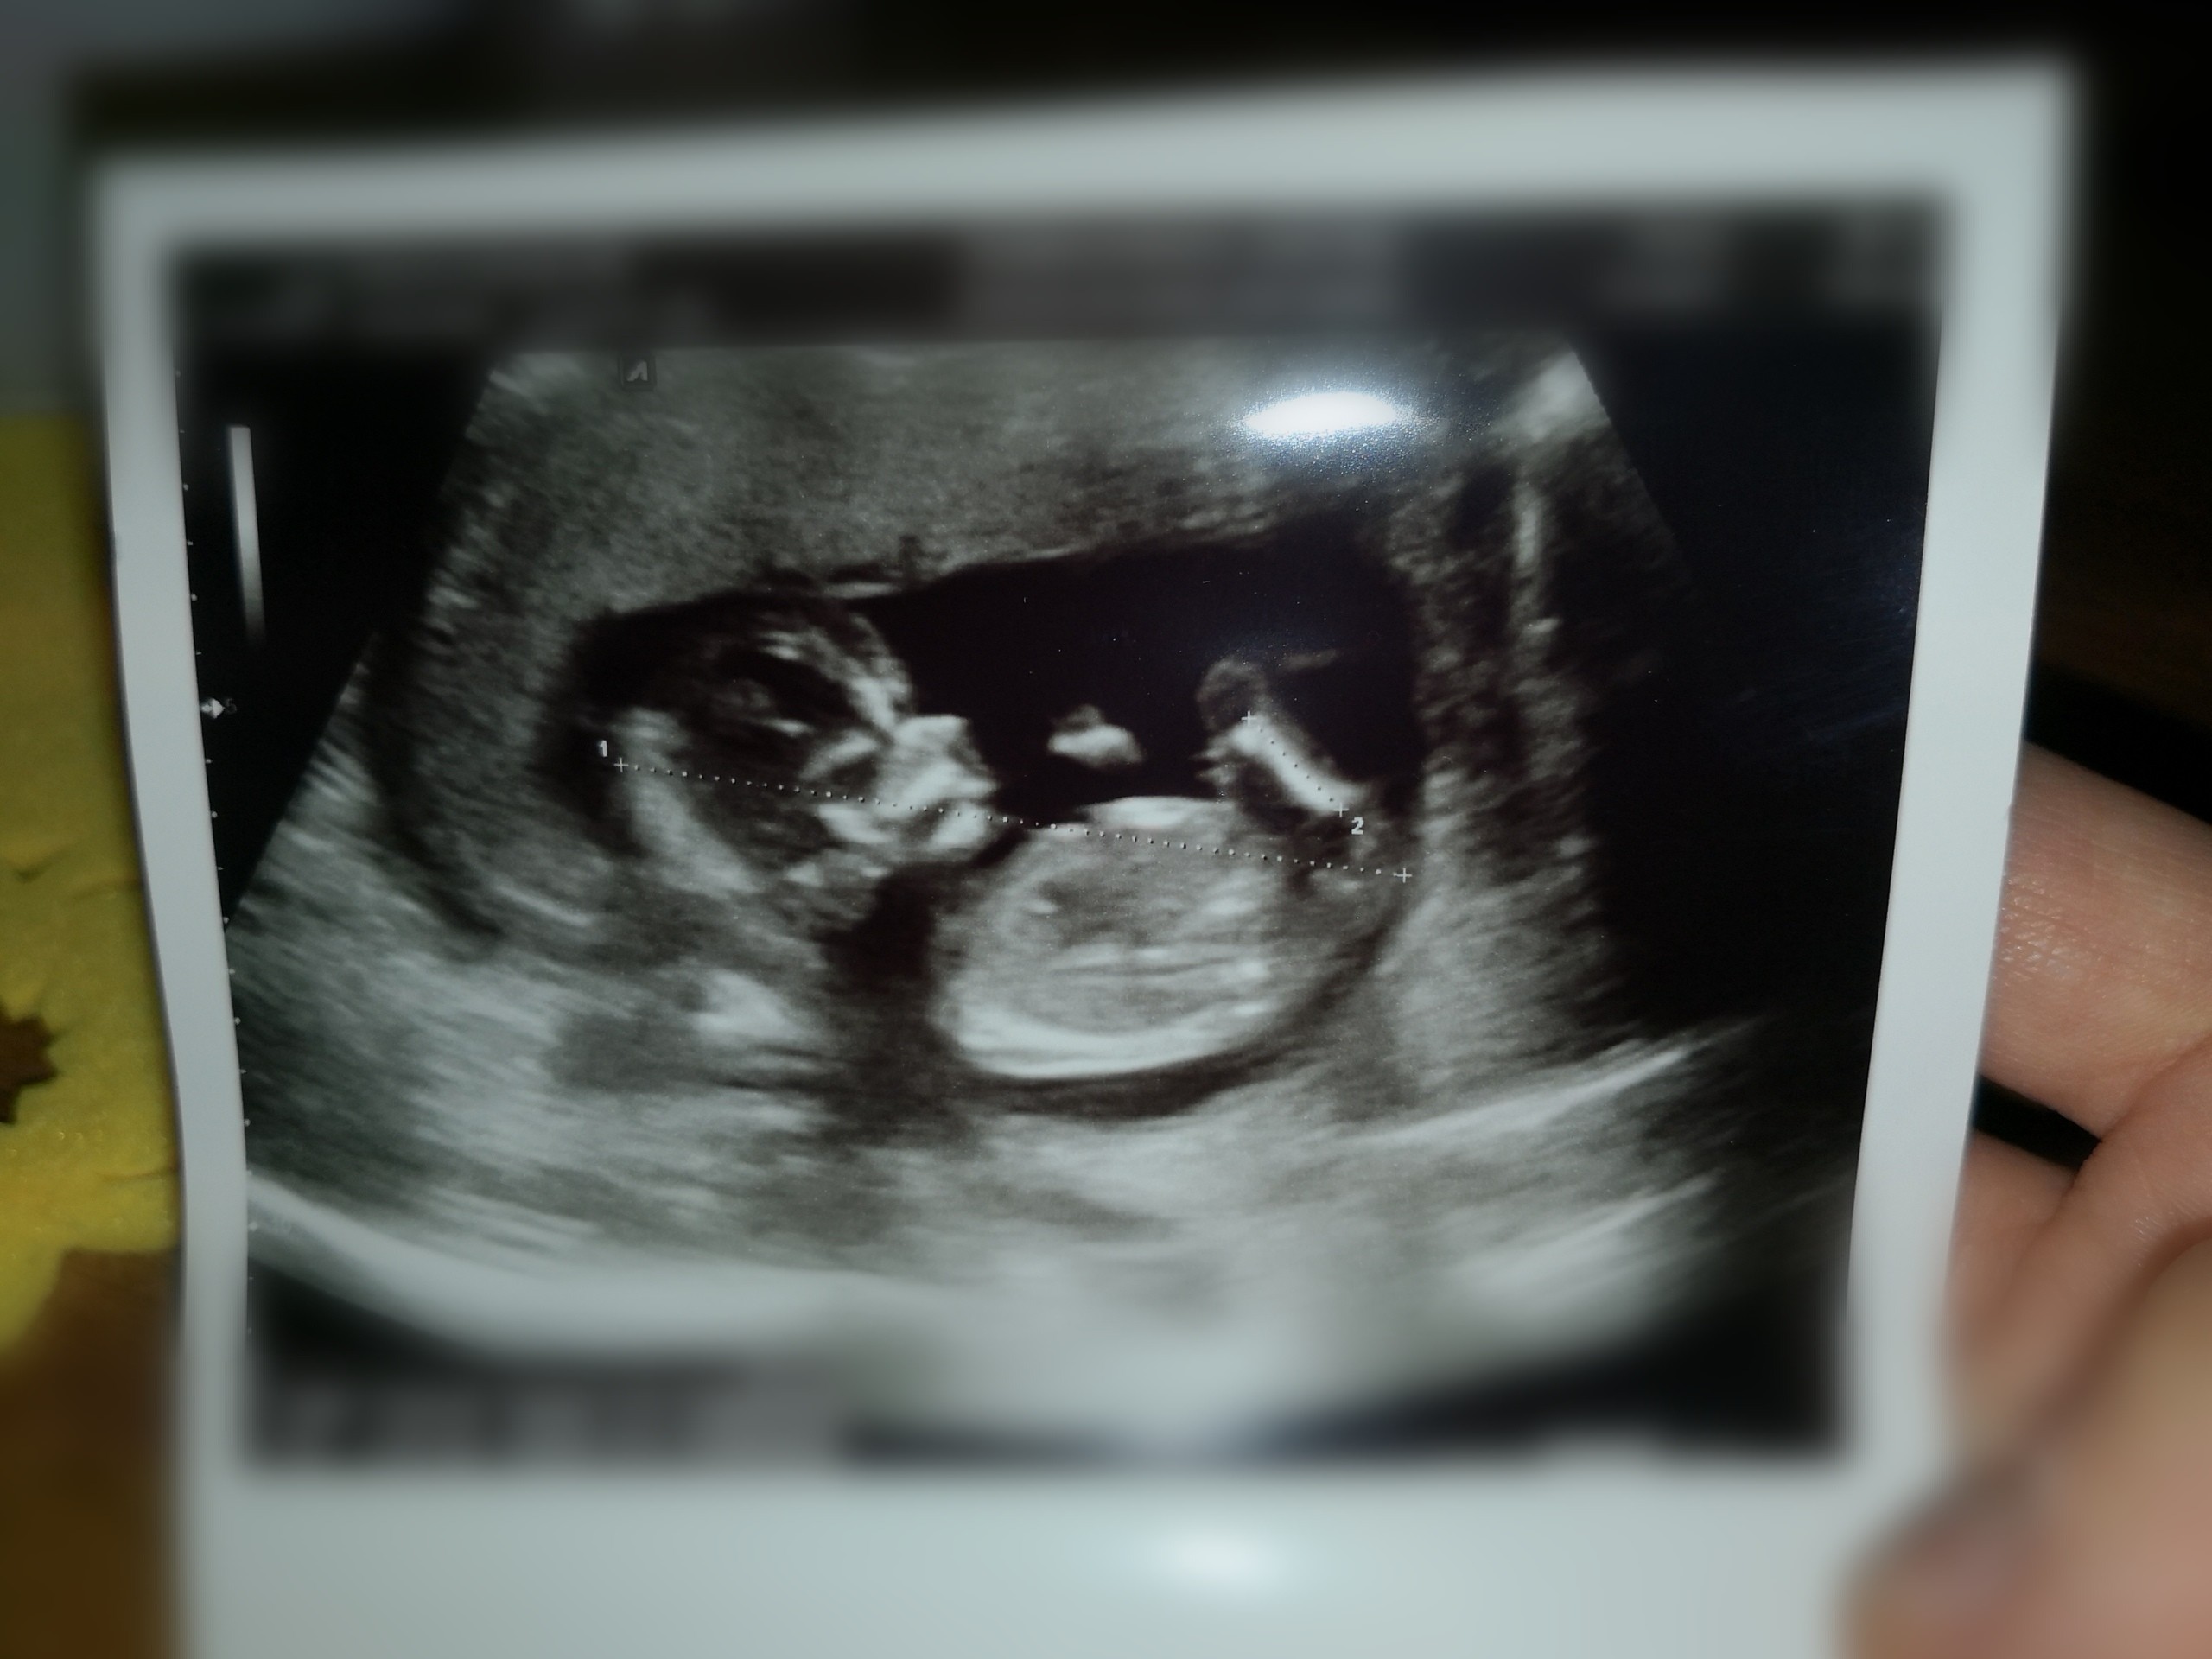

A to moje maleństwo z pn (12+3), dxidziol nie chciał współpracować.. Wykryto Arse, za 3 dni następne usg genetyczne.

Załączniki

• IMG_20200217_120347.jpeg

IMG_20200217_120347.jpeg

45,7 KB · Wyświetleń: 113

Błądząca tętnica prawa podobojczykowa... Ma to coś związane z przełykiem.. Być może z wada serduszka.. Tak naprawdę w internecie nic nie można konkretnego znaleźć, mam nadzieję że dowiem się w pn coś wiecej po kolejnym usg. Jest markerem zespołu downa też podobno... Chociaż u nas to jedyna nieprawidłowość. Trzymajcie kciuki